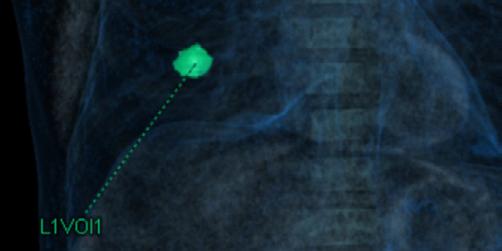

La TC de baja dosis, es la modalidad de imagen más utilizada como método de escrutinio para la detección de lesiones pulmonares, es un estudio rápido, que no requiere preparación previa. ESCANERS DE UN PACIENTE CON

Figura 1-4. Estudio de tomografía simple de tórax, con reconstrucción volumétrica, multiplanares con ventana para pulmón y en mediastino (, en donde se observa el nódulo pulmonar sólido de bordes lobulados hipodensos.

Se presente al caso de un masculino de 80 años de edad que acude por presentar tos en estudio de 3 meses de evolución, sin datos de fatiga, como antecedente de importancia tabaquismo por lapso de 40 años a razón de 1 cajetilla y media diaria (exposición de 60 paquetes año), actualmente suspendido.

Se le realiza estudio de tomografía simple de tórax en donde se encontró en el segmento anterior del lóbulo inferior derecho nódulo sólido, con diámetro de 22mm, volumen de 2.9ml, condiciona disminución del bronquio segmentario, con secreciones endoluminales distales, de acuerdo a la clasificación de LUNG RADS con categoría 4B, alta sospecha de malignidad. Sin evidencia de lesiones nodulares en el resto del parénquima.

Posteriormente, se realiza estudio de PET-CT con 18FDG , con hallazgos de metabolismo asociado y SULmax de 2.0, se recomienda realizar biopsia.

Se realiza cirugía con lobectomía inferior derecha, con resultado histopatológico de tumor carcinoide atípico, se realiza seguimiento con tomografía simple de tórax sin complicaciones en el lecho quirúrgico.

Figura 5. Estudio de PET-CT con FDG que muestra hipercaptación del radiofármaco en el nódulo pulmonar, lo que traduce en metabolismo aumentado.

Figura 6. Estudio de seguimiento postlobotomía.